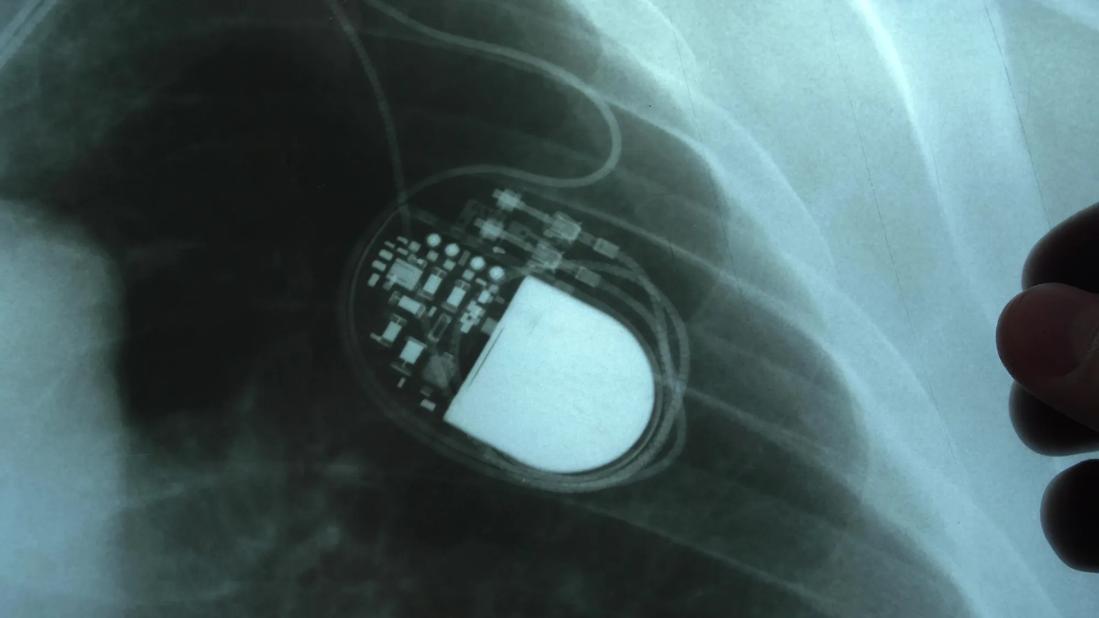

X-ray of implanted pacemaker

Pacemakers are usually inserted beneath the skin of your upper chest near your shoulder. In most cases, wires — also known as leads — run from the device into your heart. You may need one, two or three leads depending on your condition. People are usually discharged from the hospital the same day after receiving one.

• They’re surprisingly small. “Today’s pacemakers are about the size of a big tablespoon,” Dr. Varma says. That’s small enough that you’ll rarely feel it.